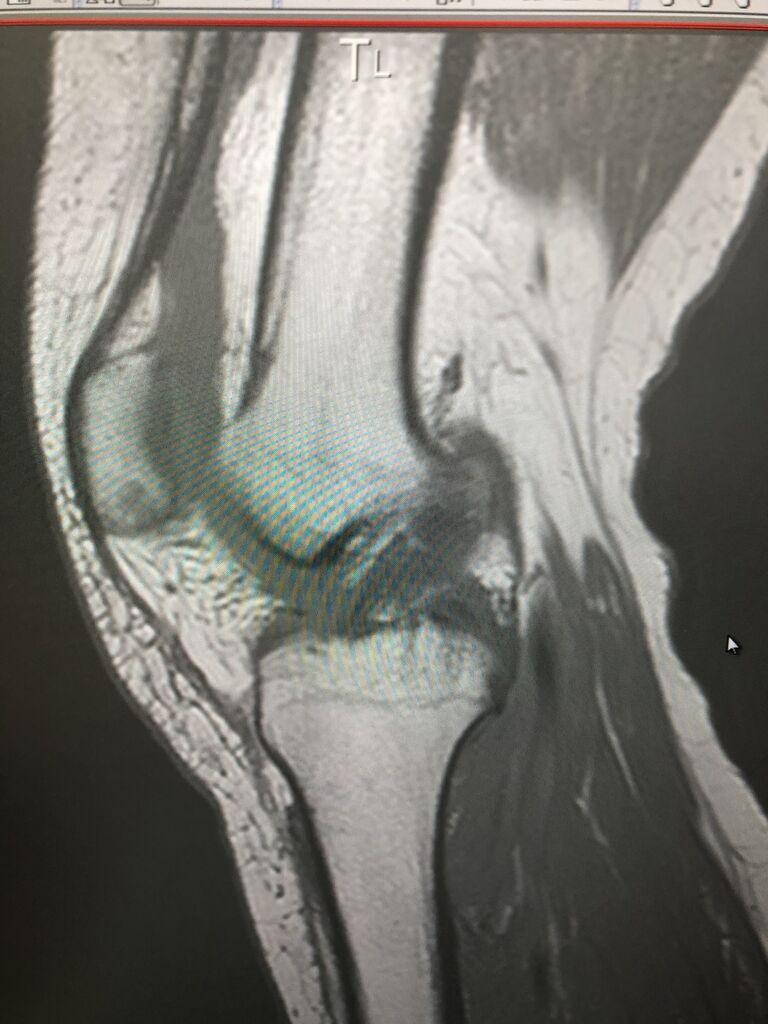

多数医療機関の診察後に、手術希望されず

当院に来院されました。 最近、そのような

患者さんが、保存的治療を求めて、よくこられます

整復後、ソフラットシーネ オールソグラス

の固定で きれいに整復され 骨癒合していきます

A38ED3A7-551B-4294-A94D-C8ADF46F558C

整復後 固定

9AAD72DB-769C-4503-AC38-A110E47164CF

これで、ずれずに

超音波骨治療器を併用で早期骨癒合します